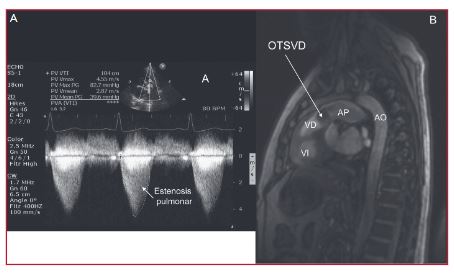

Aneurisma del seno de Valsalva con obstrucción del tracto de salida del ventrículo derecho

Los aneurismas del seno de Valsalva representan una patología infrecuente, congénita o adquirida, que puede permanecer asintomática por largo tiempo, o presentarse con complicaciones, principalmente por su rotura y la consiguiente generación de una comunicación anormal entre la aorta y otra cavidad o, más raramente, por su extensión, que lleva a la compresión o a la invasión de estructuras vecinas. En esta presentación se describe un caso de aneurisma del seno de Valsalva derecho con desarrollo de obstrucción del tracto de salida del ventrículo derecho.